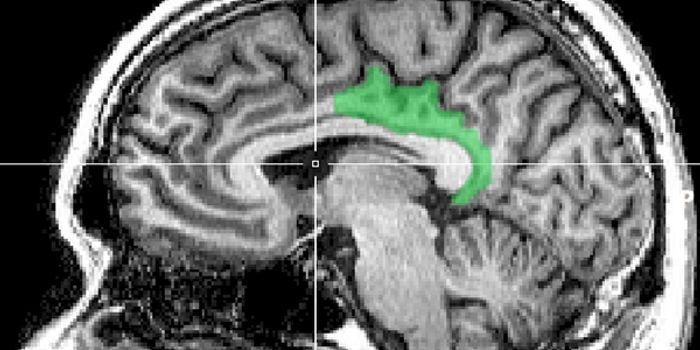

Read the latest articles about newly released neuroscience research and advances in experimental techniques. Topics include research news in neuroscience, neurology, psychology, brain science and cognitive sciences.